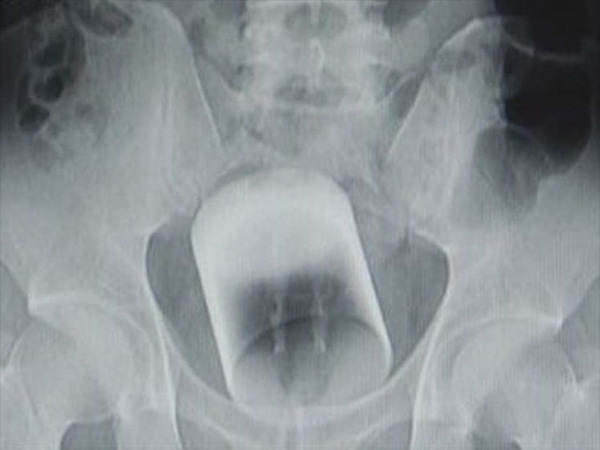

When the doctors examined the man, they were shocked to see the entire glass cup being lodged in his anus, as it had not broken. The case was complicated, as a slight breaking of the glass could cause a life-threatening harm to the man.

He Had To Be Operated…

The doctors tried to sedate his rear by giving him anaesthesia, but were not confident on pulling out the glass, as it was very slippery. Hence, they performed a surgery and removed the glass from his rear!